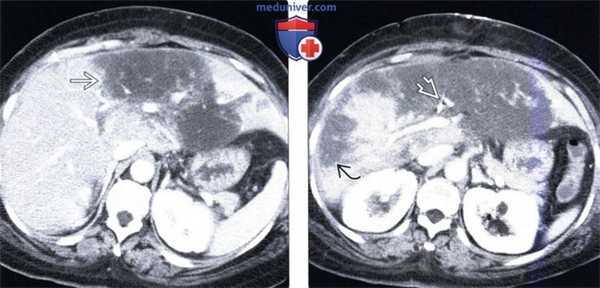

(Слева) На аксиальной КТ с контрастным усилением (реконструкция с толстыми срезами) после трансплантации печени определяется тромбоз печеночной артерии в области анастомоза, ставший причиной обширного инфаркта аллографта. Интактные участки аллографта, вероятно, кровоснабжаются ветвями воротной вены, однако через непродолжительное время у этого пациента возник некроз паренхимы печени и желчных протоков.

(Справа) На ангиограмме чревного ствола у этого же пациента определяется окклюзия печеночной артерии в области анастомоза и отсутствие артериальных кровеносных сосудов в аллографте.